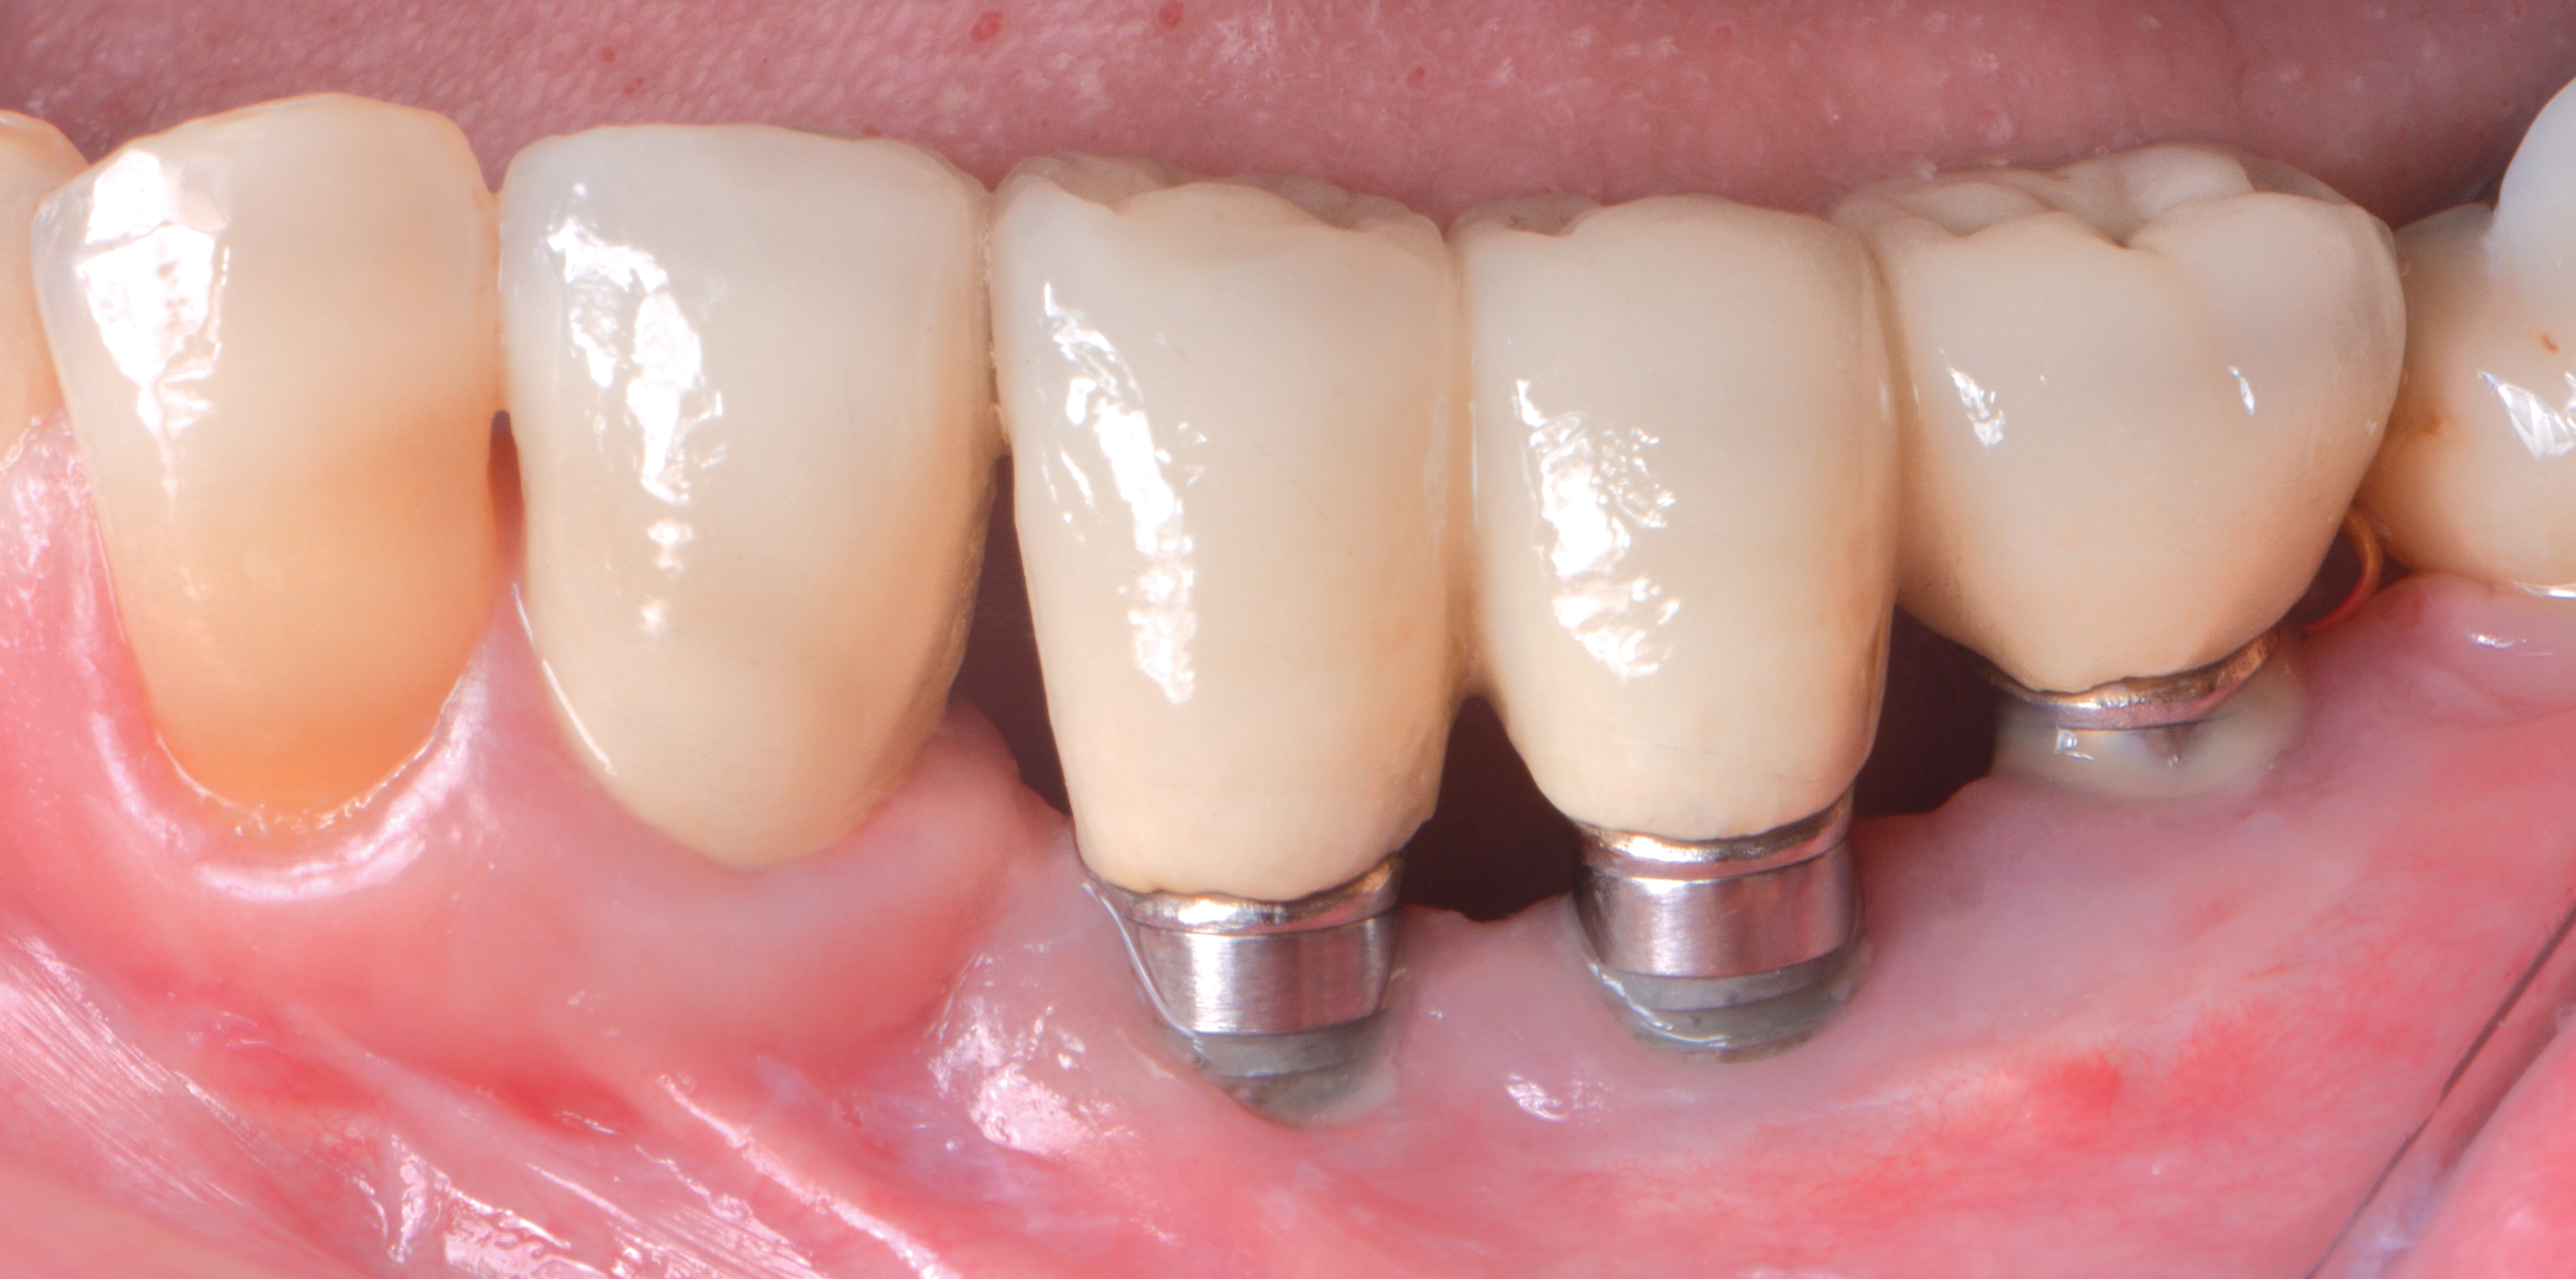

Dental implants have revolutionized the way in which clinicians treat and restore partially and fully edentulous patients and have demonstrated success for managing a broad range of clinical dilemmas. While implants have been highly predictable and have achieved long-term success, they are not immune from complications associated with improper treatment planning, poor surgical and prosthetic execution, material failure, and inadequate or infrequent maintenance. Among these problems are the biologic complications of peri-implant mucositis and peri-implantitis, which are inflammatory conditions in the soft and/or hard tissues surrounding dental implants (Figure 1 through Figure 4).1,2

Micromotion can occur at the interface of the abutment and dental implant platform for several reasons. First, incomplete seating of the abutment can leave a gap and fail to provide adequate clamping force. Second, micromotion could be related to loosening of the screw securing the abutment to the implant, which may result from excessive occlusal force or inadequate torque being provided to fully tighten the screw. Third, this may be the result of using aftermarket parts or trying to mix and match between systems. In all three instances, the lack of intimate fit predisposes the site to micromotion, leading to inflammation and potential for marginal bone loss.

An abutment fitting poorly to the implant platform can facilitate plaque accumulation due to the nature of the margin being open. A number of articles have discussed the benefit of keeping the interface between the implant platform and the abutment as free of plaque accumulation as possible. In fact, this is the general thought process behind platform switching. Anything that hinders this by enhancing inflammation will be detrimental to the health of the implant. The easiest way to avoid this is to expose a radiograph at the time of prosthesis insertion and periodically thereafter to verify a well-fitting abutment/implant platform interface.